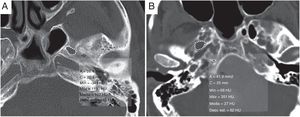

Otros hallazgos radiológicos asociados a aumento de presión del LCREnsanchamiento del foramen ovalLa presión de LCR elevada crónicamente puede producir remodelación y erosión ósea, hallazgo que se evidencia en el ensanchamiento del foramen oval (FO). El área media de este es mayor en pacientes con HII (fig. 5). Para un valor de corte de 30 mm2, la sensibilidad del área del FO para detectar HII es del 50%, con una especificidad del 81%. Para un valor de corte de 40 mm2, la especificidad y el valor predictivo positivo son del 100%15.

Aumento del área del foramen oval. A) Área del foramen oval en tomografía computarizada de cabeza sin contraste en paciente sano, con valor de 26,4 mm2. Compárese con un paciente con hipertensión intracraneal idiopática (B) en el que el área media del foramen oval es de 41,9 mm2, mayor de 40 mm2.